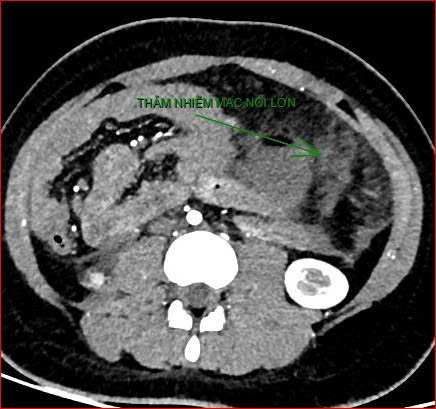

Khoảng 21 giờ 40, kết quả chụp CT cho thấy bệnh nhân rơi vào tình trạng cực kỳ nặng và hiếm gặp, bao gồm: xoắn dạ dày, nhồi máu thận trái, nhồi máu lách, viêm đầu tụy, viêm hỗng tràng, kèm dịch ổ bụng và tràn dịch màng phổi, trên nền bệnh nhân mắc hội chứng Down và tim bẩm sinh.

Hình ảnh chụp CT ổ bụng cho thấy dạ dày giãn lớn, xoắn bất thường; kèm tổn thương nhồi máu lách và viêm tụy trên nền ca bệnh hiếm, diễn biến đặc biệt nặng - Ảnh Bệnh viện cung cấp